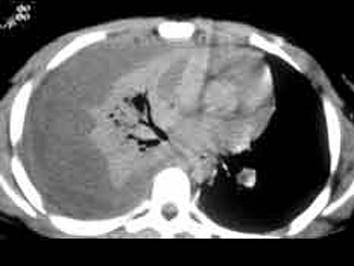

下列图像最佳诊断是什么 ( )A、肺癌B、血胸C、气胸D、脓胸E、肺不张

选项 A、肺癌 B、血胸 C、气胸 D、脓胸 E、肺不张

答案 D